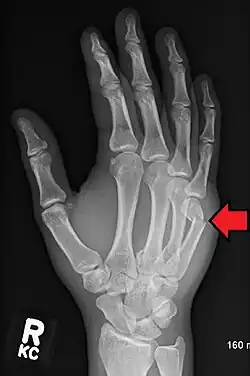

Boxer's fracture of the 5th metacarpal head from punching a wall

Classically, it occurs after a person hits an object with a closed fist.[3] The knuckle is then bent towards the palm of the hand.[3] Diagnosis is generally suspected based on symptoms and confirmed with X-rays.[3]

Diagnosis by a doctor's examination is the most common, often confirmed by x-rays. X-ray is used to display the fracture and the angulations of the fracture. A CT scan may be done in very rare cases to provide a more detailed picture.